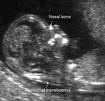

שקיפות עורפית היא בדיקת אולטרהסאונד המבוצעת על מנת לשלול סינדרום על שם דאון ומומי לב בעובר.

הבדיקה מבוצעת בשב' 11-14 בעוברים שאורכם 38 עד 84ממ'

הבדיקה מתאפשרת מאחר ובשבועות אלו מצטבר נוזל מתחת לעור העובר באזור העורף והגב. עובי האזור עם הנוזל הוא האזור הנמדד במהלך הבדיקה.''על הבדיקה עצמה:

על מנת לקבל מדידה אחידה בין הבודקים מקפידים הבודקים על מספר כללים שפותחו על ידי חוקרים. הכללים כוללים שימוש בהגדלה, מראה העובר בפרופיל, מדידת עובי השקיפות בצורה אחידה ועוד.

בתמונה למטה סימנתי את השקיפות עם שתי צלבים ורשמתי NT ליד.

באופן כללי, עובי שקיפות עד 3 ממ' נחשב כתקין.

במהלך בדיקת השקיפות יש רופאים הבודקים האם עצם האף בעובר קיימת או לאו ויש גם כאלו המודדים את קצב הלב.